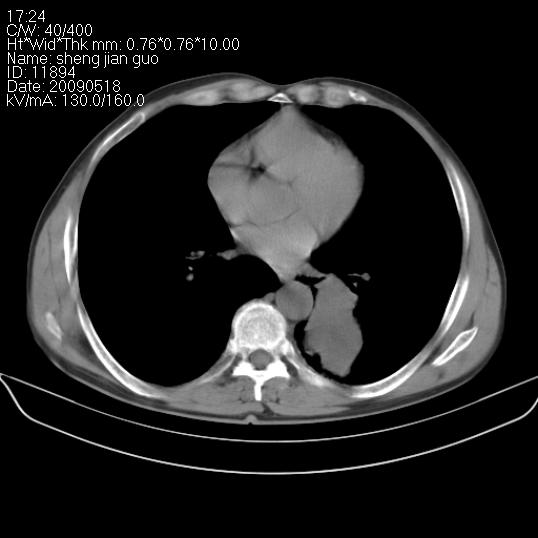

以下是引用zjzjr在2009-5-19 17:25:00的发言:[br]支持楼主考虑,另左肺下叶阻塞性炎症。

以下是引用zhao_bin2008在2009-5-19 17:48:00的发言:[br]支持左肺下叶周围型肺癌并阻塞性肺炎。

以下是引用杀毒软件在2009-5-19 17:36:00的发言:[br]支持楼主

以下是引用zsl6918在2009-5-20 7:10:00的发言:[br]左侧中心型肺癌!